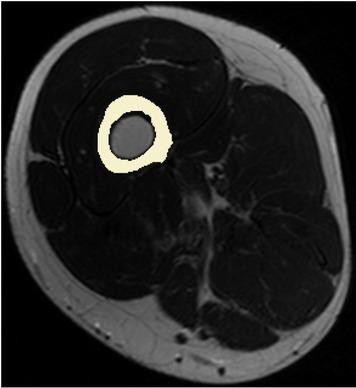

Fig. 2